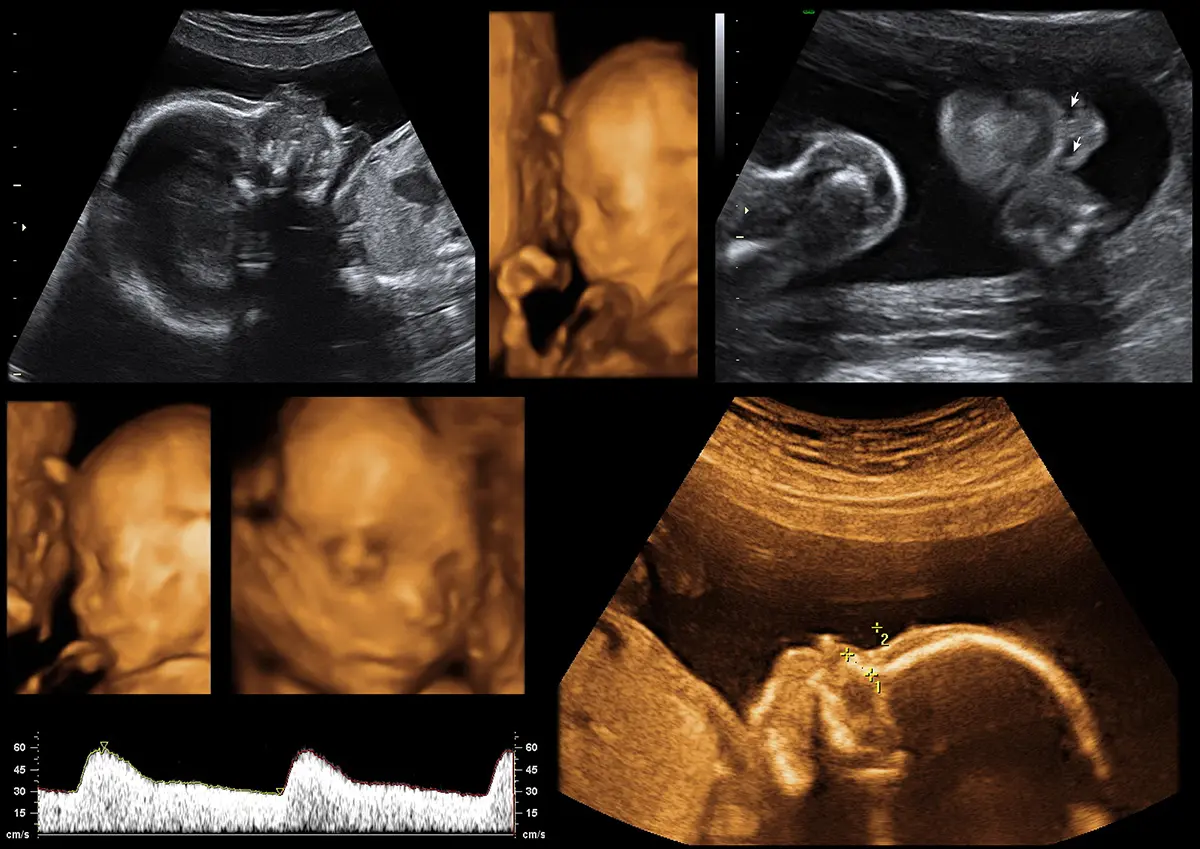

Mini Anomaly Scan je ciljani ultrazvučni pregled fetusa koji se provodi tijekom trudnoće radi brze i usmjerene procjene osnovnih fetalnih anatomskih struktura. Pregled ne zamjenjuje detaljni anomaly scan, već služi kao dopunska ili kontrolna pretraga prema kliničkoj indikaciji.

Osnovna morfologija fetusa uključujući: glavu i moždane strukture, kralježnicu, prsni koš, srce u osnovnim presjecima, abdomen, želudac i mokraćni mjehur, ekstremitete te količinu plodne vode i položaj posteljice.

Najčešće između 18. i 24. tjedna trudnoće, kao kontrolni pregled između redovitih ultrazvučnih pregleda ili kod potrebe za brzom procjenom fetalne anatomije.

Mini Anomaly Scan nije zamjena za detaljni anomaly scan i ne uključuje iscrpnu analizu svih fetalnih struktura niti detaljnu ehokardiografiju fetusa. Nalaz se uvijek interpretira u kontekstu gestacijske dobi i prethodnih pretraga.